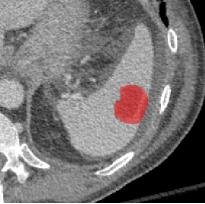

Early tumor detection save lives. Each year, more than 300 million computed tomography (CT) scans are performed worldwide, offering a vast opportunity for effective cancer screening. However, detecting small or early-stage tumors on these CT scans remains challenging, even for experts. Artificial intelligence (AI) models can assist by highlighting suspicious regions, but training such models typically requires extensive tumor masks--detailed, voxel-wise outlines of tumors manually drawn by radiologists. Drawing these masks is costly, requiring years of effort and millions of dollars. In contrast, nearly every CT scan in clinical practice is already accompanied by medical reports describing the tumor's size, number, appearance, and sometimes, pathology results--information that is rich, abundant, and often underutilized for AI training. We introduce R-Super, which trains AI to segment tumors that match their descriptions in medical reports. This approach scales AI training with large collections of readily available medical reports, substantially reducing the need for manually drawn tumor masks. When trained on 101,654 reports, AI models achieved performance comparable to those trained on 723 masks. Combining reports and masks further improved sensitivity by +13% and specificity by +8%, surpassing radiologists in detecting five of the seven tumor types. Notably, R-Super enabled segmentation of tumors in the spleen, gallbladder, prostate, bladder, uterus, and esophagus, for which no public masks or AI models previously existed. This study challenges the long-held belief that large-scale, labor-intensive tumor mask creation is indispensable, establishing a scalable and accessible path toward early detection across diverse tumor types. We plan to release our trained models, code, and dataset at https://github.com/MrGiovanni/R-Super